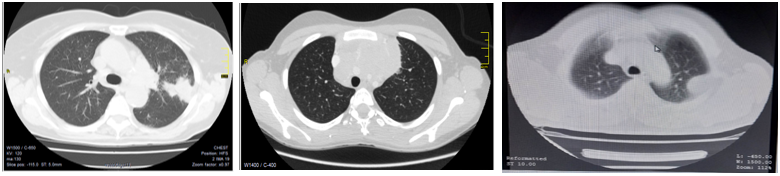

The percutaneous biopsy of Tumor-like lesions of the thoracic cavity under images have become an essential tool in cancer medicine for the study, staging, and therapeutic planning. Since the first report of the technique in 1976 there has been great progress in the development of biopsy instruments, as well as imaging equipment. Computed tomography (CT) is the modality of choice to guide percutaneous biopsy of central tumor-like lesions in the thoracic cavity or surrounded by aerated lung. However, throughout history its use included peripheral lesions with pleural contact (Image 1 - Image 2).

Image 3 Chest CT images in soft tissue window. Image A. Prebiopsy of left pulmonary nodule. B. Prebiopsy of anterior superior mediastinal widening. C. Prebiopsy of left subpleural lesion.